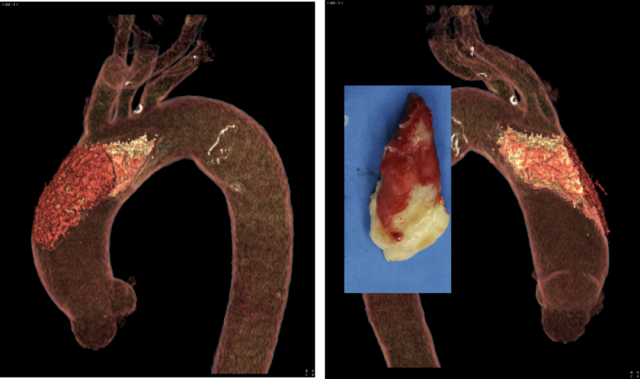

经过进一步检查发现,发病原因竟然是升主动脉内长了「肿瘤」?之后来到安贞医院完善主动脉 CTA 检查,结果确实发现在升主动脉腔内漂着一个「肿瘤」,长径大约 4 cm,出血脑梗死可能就是这个「肿瘤」部分脱落导致血管梗塞。

我的主治医生告诉我儿子:我这病情(主动脉肿瘤)可实属罕见。于是当天他们赶紧组织了临床影像联合会诊。并基于术前诊断:主动脉漂浮血栓,鉴于病变比较大,已经发生重要脏器血管堵塞事件,于是实施手术治疗,术后病理也证实为主动脉血栓。